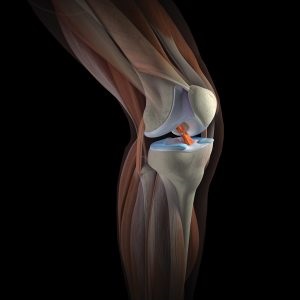

Cunoștințe imagine normală cu ultrasunete pentru a evalua structurile intraarticulare si periarticulare ale genunchiului. Unul dintre avantajele cheie ale mamografie cu ultrasunete în situații de urgență și de urgență este abilitatea de a vizualiza tesuturilor moi. In raze X vizibile numai structurile osoase convenționale implicate în formarea genunchiului (femur, tibie și patela). A structuri moi și cartilaginoase (cartilagiile, capsulă, ligamente) sunt invizibile.

In contrast tehnici radiografice folosind ultrasunete poate examina în detaliu structura ligamentelor și aparatelor meniscuri. Acest lucru este valabil mai ales cu leziuni sportive la sportivi, jucători de fotbal, halterofilii și powerlifters.

mișcare stângace, traume, exercitarea excesivă, însoțită de rotație a piciorului de-a lungul axei longitudinale, poate provoca deteriorarea meniscuri și ligamentelor. Această condiție se manifestă durere severă, modificări în configurații comune și restricții importante de circulație. Atunci când incapacitatea de a efectua diagnosticul IRM cu ultrasunete ajuta pentru a oferi o evaluare adecvată a prejudiciului și decide cu privire la tactici suplimentare de tratament.

Rotula este un os sesamoid, care se află în interiorul tendonul cvadriceps femural. Datorită naturii acestui prejudiciu aranjament la rotula nu este întotdeauna diagnosticat prin examene radiologice. În acest caz, puteți utiliza cu ultrasunete.